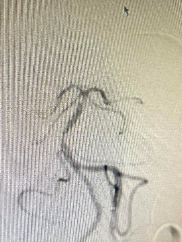

既往影像检查

重要影像结论:3月前脑血管造影左侧大脑中动脉闭塞